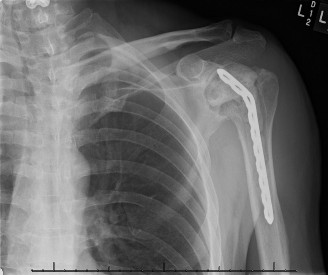

The patient undergoes resection arthroplasty with antibiotic cement spacer and a 6-week course of IV antibiotics. He returns to clinic 4 months later with improved pain, CRP <3, however, on examination he has a positive belly press sign and increased external rotation compared with the contralateral shoulder. Imaging is shown in Figure 2–57.

Figure 2–57

The correct answer is (D). The patient has completed his course of antibiotics and his spacer and is now an appropriate candidate for explanation of the cement spacer with revision shoulder arthroplasty, therefore Choices A and C are incorrect. The patient’s clinical examination findings point to rotator cuff tear (specifically subscapularis) which has occurred in the interval between his obtaining his initial total shoulder arthroplasty and his current examination. Therefore, total shoulder arthroplasty (Choice B) is contraindicated, and the patient should have a reverse total shoulder arthroplasty. Objectives: Did you learn...? Recognize the clinical presentation of a patient with infection after total shoulder arthroplasty?